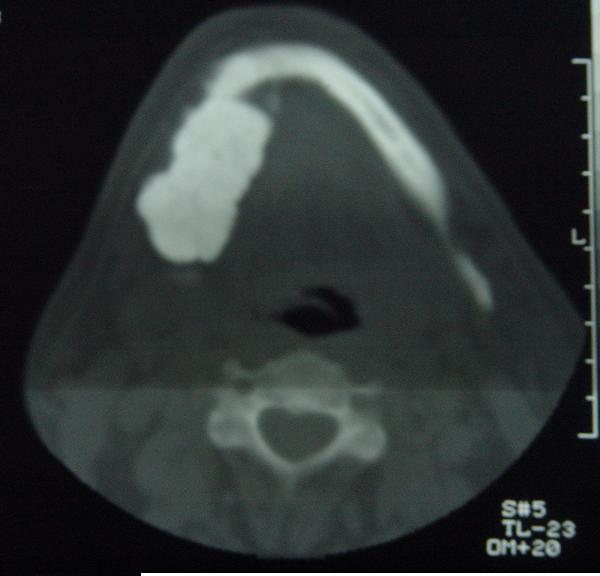

标题: CT12465:下颌骨肿瘤,请会诊 [打印本页]

标题: CT12465:下颌骨肿瘤,请会诊

发现下颌骨肿瘤近30年.逐渐增大.

造釉细胞瘤,没有特征性;半月切迹?骨间隔?多房性骨密度减低区,大小不等。鉴别;动脉瘤样骨囊肿,骨软骨瘤。本人,更倾向于---骨软骨瘤。

考虑右侧下颌骨骨化性纤维瘤。